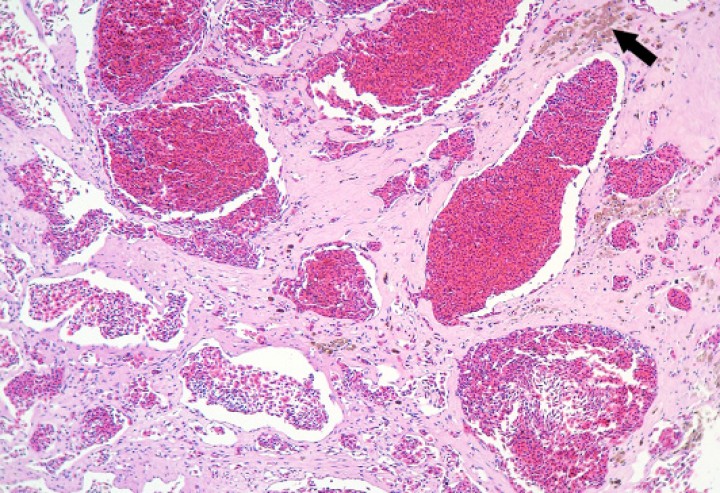

Se diagnosticó colelitiasis en la vesícula biliar de 4 sapillos baleares (Alytes muletensis) (4/131; 3,1%), con cálculos de hasta unos 6 mm de diámetro y sin evidencias de enfermedad obstructiva de vías biliares con excepción de un paciente. En este, la colelitiasis se acompañó de distensión prominente de la cavidad celómica (Fig. 15) debida a dilatación marcada de la vesícula biliar (Fig. 16) y de los conductos biliares intrahepáticos, con ruptura de la vesícula biliar y embolismo de bilis en el seno linfático subcutáneo, así como colangiohepatitis bacteriana ascendente de vías biliares secundaria a la presumible enfermedad biliar obstructiva. La bilis embolizada en el seno linfático, que contenía abundantes bacterias, causó engrosamiento de los tejidos blandos de la extremidad posterior izquierda (Fig. 15), donde se acompañó de necrosis muscular y cutánea (Fig. 17).

<p>Extremidad posterior; sapillo balear (<em>Alytes muletensis</em>). El seno linfático subcutáneo (delimitado con cabezas de flecha) está dilatado por abundante secreción biliar (con bacterias), lo cual se acompaña de necrosis de la dermis (asteriscos) y del músculo subyacente (m); con frecuencia, las fibras musculares necróticas están fragmentadas. Hematoxilina-eosina, x48.</p>

Extremidad posterior; sapillo balear (Alytes muletensis). El seno linfático subcutáneo (delimitado con cabezas de flecha) está dilatado por abundante secreción biliar (con bacterias), lo cual se acompaña de necrosis de la dermis (asteriscos) y del músculo subyacente (m); con frecuencia, las fibras musculares necróticas están fragmentadas. Hematoxilina-eosina, x48.